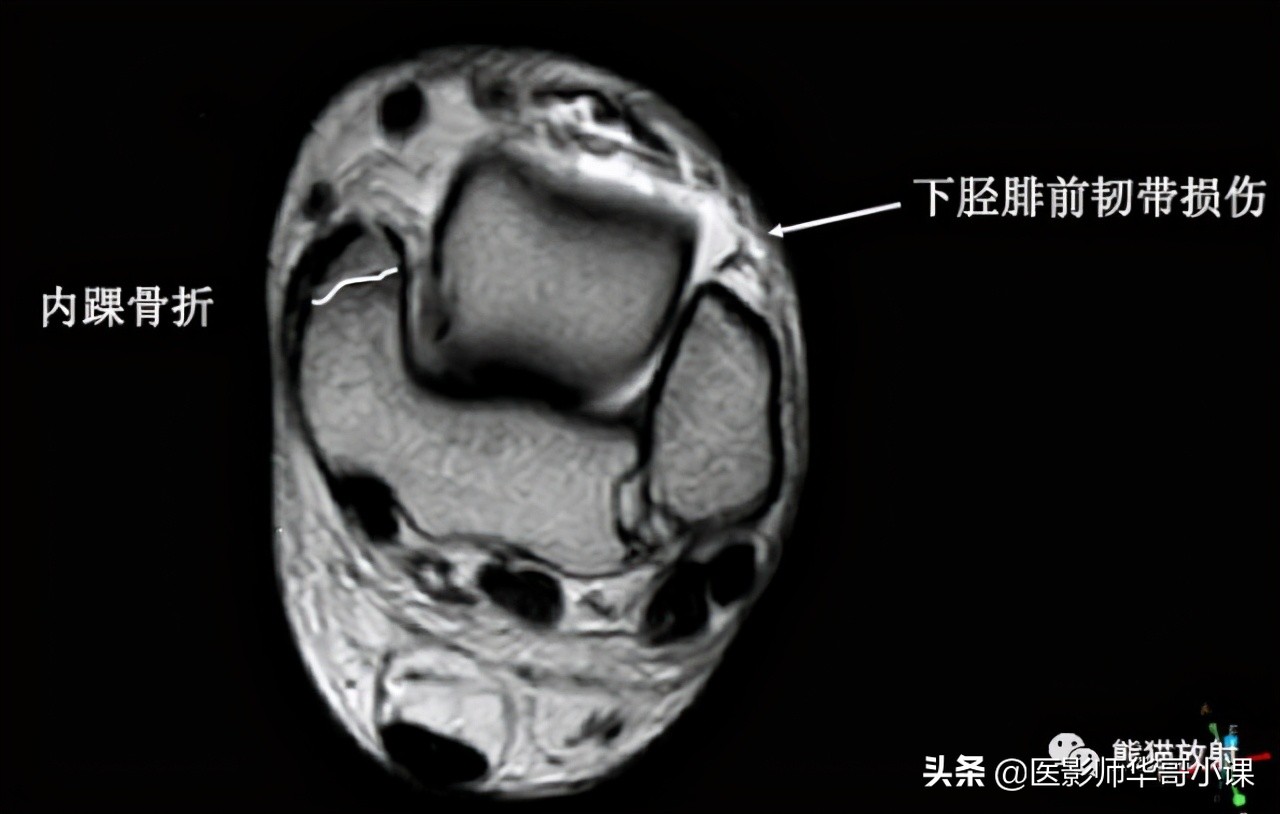

下胫腓联合韧带

胫腓骨远侧关节面由腓骨远端的凸面和胫骨远端的凹面组成,由胫腓韧带链接,关节内无软骨结构。 远端胫腓联合韧带由四部分韧带组成,包括: 骨间韧带,下胫腓前韧带,下胫腓后韧带,下横韧带。

骨间韧带由骨间膜远端增厚形成。下胫腓前韧带起于胫骨结节的前外侧,止于腓骨脊的前侧。下胫腓后韧带起于胫骨脊后侧,止于外踝后缘。下横韧带组成下胫腓后韧带的下半部分,可视为下胫腓后韧带的一部分。

下胫腓联合韧带损伤的机制 通常是踝关节外旋和过度背屈。可以导致下胫腓联合损伤的运动包括运动(足球等),低能量创伤等。外旋损伤通常发生于踝关节旋前或旋后位。胫腓联合韧带损伤可以单发或者合并骨折。